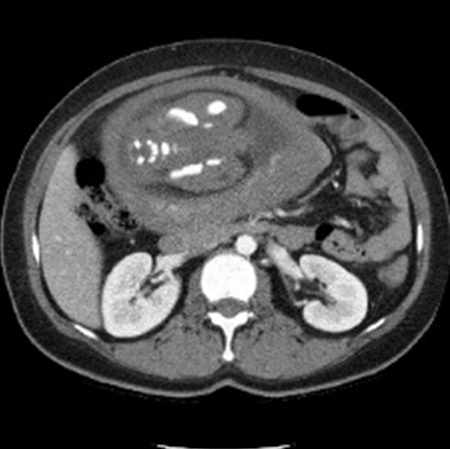

After completing radiation therapy, the patient visited our oncology clinic for a physical examination to evaluate her treatment response. Her vital signs were normal (blood pressure: 120/89 mmHg; pulse rate: 65 times/min; respiratory rate: 16 times/min; and body temperature: 37.4°C). She was clearly alert, but pale conjunctiva was noted on physical examination of the head and neck region. Her heart sounds were normal on chest auscultation, and her breathing sounds were also normal. No mass, tenderness, or rebound tenderness were found on abdominal examination except that abdominal distension was observed. The liver and spleen were not palpable, but the lower abdomen was soft and was slightly hard on palpation. No other abnormal findings, such as pretibial pitting edema, were observed. A peripheral blood test showed that the hemoglobin level had decreased to 10.9 g/dL (mean corpuscular volume, 85.0 fL; mean corpuscular hemoglobin, 28.0 pg; and mean corpuscular hemoglobin concentration, 32.9 g/ dL). Other values were as follows: white blood cell count, 10,000/μL; neutrophil, 81.7%; platelet, 224,000/μL; and erythrocyte sedimentation rate, 30 mm/hr. Blood chemistry for liver and renal function was normal and no other abnormal findings were noted. No findings of residual cancer were noted on imaging studies, but a fetal outline was observed on chest CT imaging conducted for response assessment at 32 weeks after surgery (Figure 1). Thus, abdominal ultrasound examination was performed and the following findings were made: biparietal diameter, 6.7 cm; head circumference, 25.3 cm; abdominal circumference, 26.3 cm; femoral length, 5.8 cm; amniotic fluid index, 9.4, and predictive fetal weight, 1,450 g. The obstetric examinations confirmed that gestational age was approximately 29 weeks and the fetus was in good condition. Although the date of last menstruation was not accurate and she did not know the conception time, considering the gestational age on ultrasound, she was estimated to have been pregnant during the early stage of adjuvant chemotherapy or immediately after surgery.

Figure 1: Intrauterine pregnancy was identified in the chest CT scan at 32 weeks after surgery.